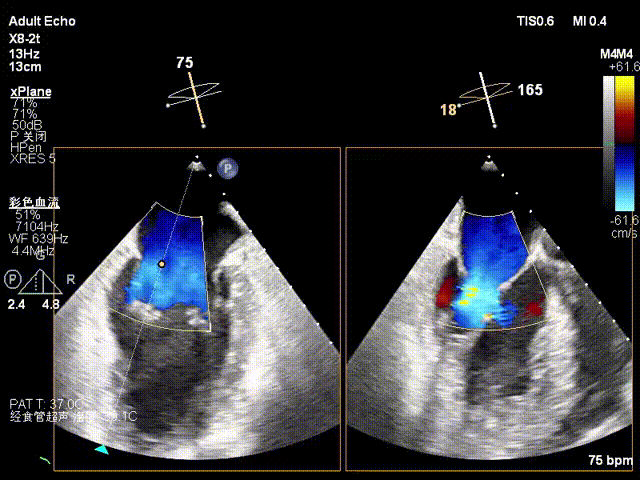

二尖瓣前叶长度26.3mm,后叶长度17.7mm,对合高度约6mm,对合深度约9.5mm,VC 7.0mm,MVA 6.7cm²。

患者全麻后,在经食道超声心动图和X射线引导下,经股静脉入路,将申淇淇麟®系统瓣膜夹顺利送至二尖瓣A2/P2区域,经调整位置使瓣膜夹垂直对合缘,跨瓣,应用单瓣叶独立捕获功能,成功地分别捕捉二尖瓣前叶和后叶,经超声心动图反复确认瓣叶夹持牢固,反流量减少,跨瓣压差3mmHg。遂释放瓣膜夹,超声心动图评估瓣膜夹位置和功能良好,瓣膜夹活动度低,手术顺利完成。

TEE显示,二尖瓣夹植入后反流减少